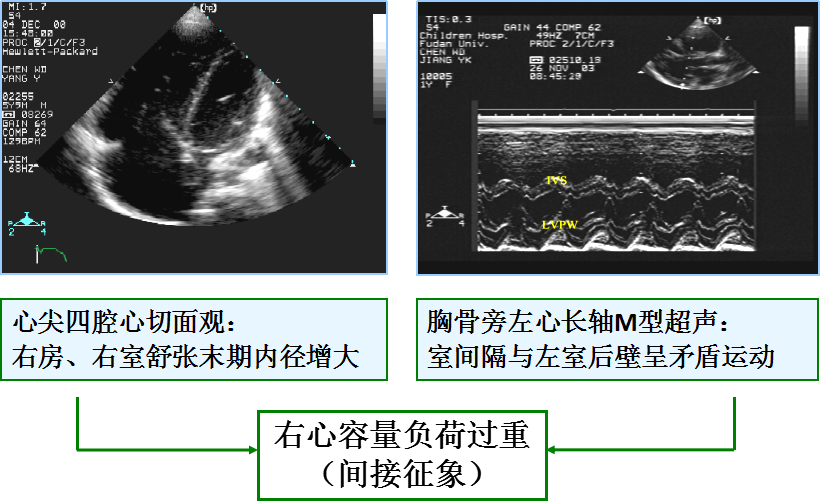

(间接征象)